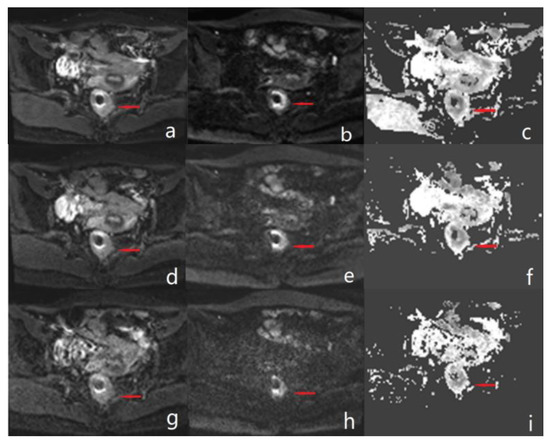

3.3. Quantitative Image Quality Analysis